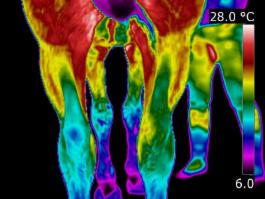

Equine Infrared Thermal Imaging or Thermography is a non-invasive, non-contact, tool that uses the very latest infrared imaging equipment and computer software to detect minute differences in the horse’s thermal and neural condition. Thermography is a qualitative assessment of temperatures. The infrared camera measures heat emissions from the body, visible as a thermal image. It can quickly and efficiently identify areas that may require further investigation. Your vet can then make a decision on any treatment needed and thermography can then be used to monitor the recovery. |

Infrared

Equine Thermography will help you to build an accurate picture of what

is going on beneath the surface of an individual horse. It provides the

horse owner and equine professional with an advanced visual aid with

which to locate heat, inflammation, tissue tone, cold, reduced blood

circulation and some affected nerve functions. A valuable addition to

existing diagnostic tools, thermal imaging is non-invasive, emits no

radiation and can be repeated as frequently as required.